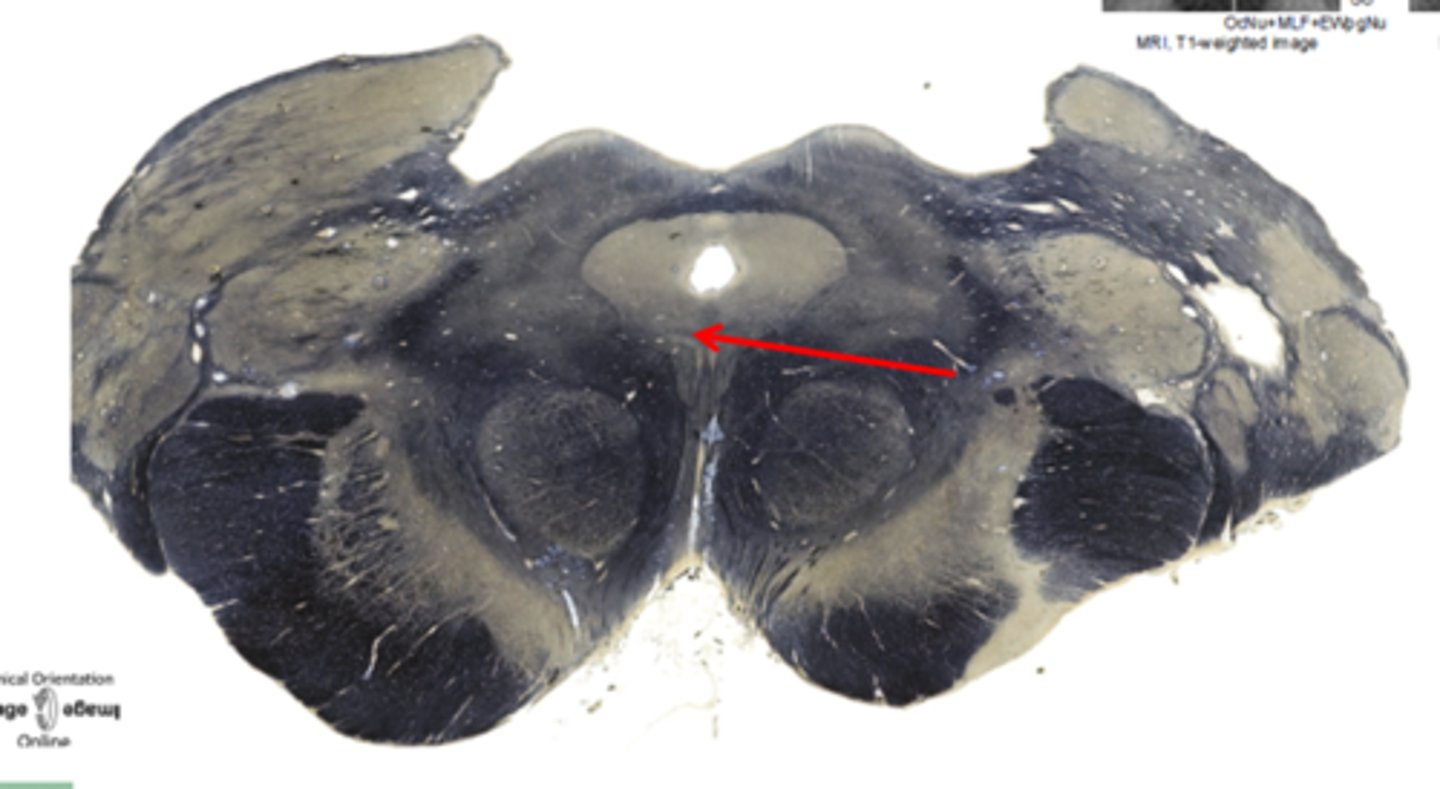

oculomotor nucleus in the midbrain

controls eye movements & pupillary constriction

trochlear nucleus

controls superior oblique eye muscles

Edinger-Westphal nucleus

part of oculomotor complex controlling ciliary muscle for accommodation of the lens & pupil constriction